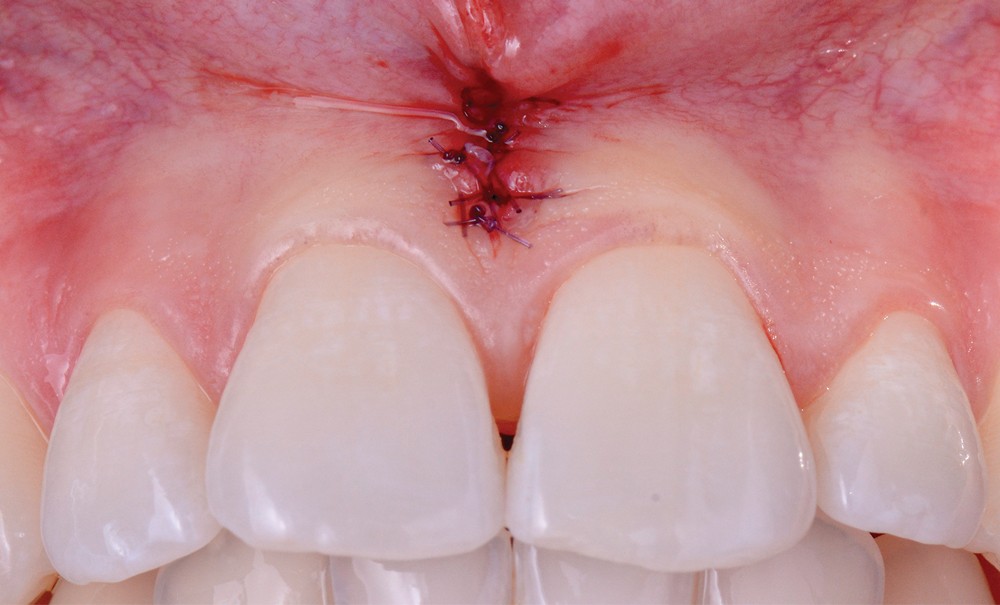

À l’état sain, la papille occupe la totalité de l’espace interdentaire. Elle est délimitée par l’os alvéolaire en apical, le sommet de la papille, et les faces proximales des dents (fig. 1).

Lors du sourire forcé, la papille interdentaire est visible chez 91 % des patients et chez 87 % des patients ayant pourtant une ligne de sourire gingivale basse [1]. Ainsi, les papilles jouent un rôle important dans l’expression du sourire ; rétablir l’équilibre du blanc sans prendre en compte le rose ne permettra pas d’obtenir un résultat esthétique satisfaisant pour les patients [2]. Une étude a été menée pour analyser les critères perçus comme esthétiques ou inesthétiques de la part d’individus. 80 personnes ont analysé des images digitales et répondu via des questionnaires. Cette étude a révélé que la présence de trous noirs interdentaires est le troisième critère perçu comme le plus inesthétique (après les caries et les limites coronaires visibles) [3].

La papille tient plusieurs rôles, tant esthétiques que fonctionnels. L’espace laissé vacant par l’absence de papille peut perturber la phonation ou être à l’origine de passages d’air et de salive (postillons), voire de tics d’aspiration (fig. 2a-b). Cette zone noire attire le regard et les patients rapportent qu’ils font régulièrement l’objet de remarques : ils…